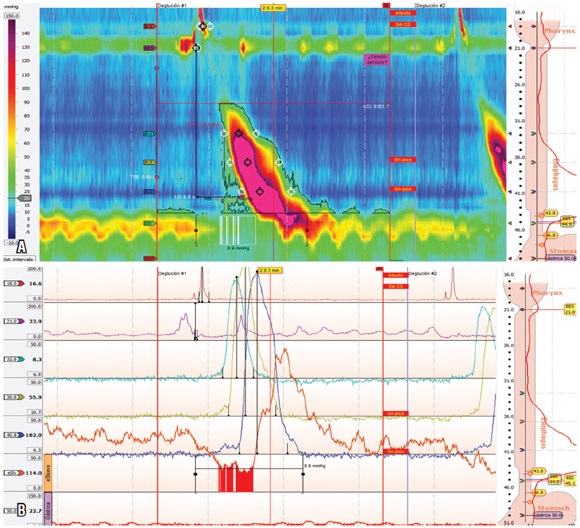

Paciente masculino de 73 años con antecedente de ERGE de larga data, con síntomas típicos que se habían tornado refractarios a IBP, sin disfagia ni dolor torácico. El estudio endoscópico reveló hernia hiatal sin esofagitis y presbiesófago. El estudio con MAR encontró 8 de 12 ondas multipico, todas con un ICD superior a los 5000 mm Hg/cm/s y 4 por encima de 8000 mm Hg/cm/s, siendo la más alta de 16285 mm Hg-s-cm. Este paciente presentó además una presión intrabolo elevada (26 mm Hg) (tablas 1 y 2; figura 4).